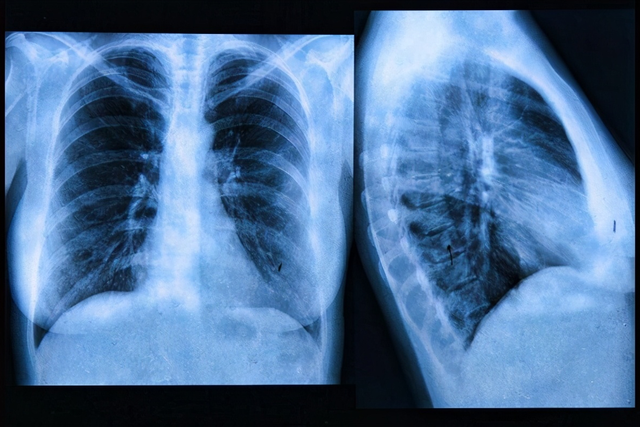

肺 , 这个我们身体里面特别重要的器官 , 它就像一个不停工作的泵 , 不断地给我们的身体输送氧气 , 同时又排出二氧化碳 。 你可能听说过很多保护心脏的方法 , 但其实 , 肺部的健康同样重要 , 尤其是对于上了年纪的朋友们 。